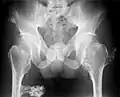

multiple osteochondromas at the pelvis